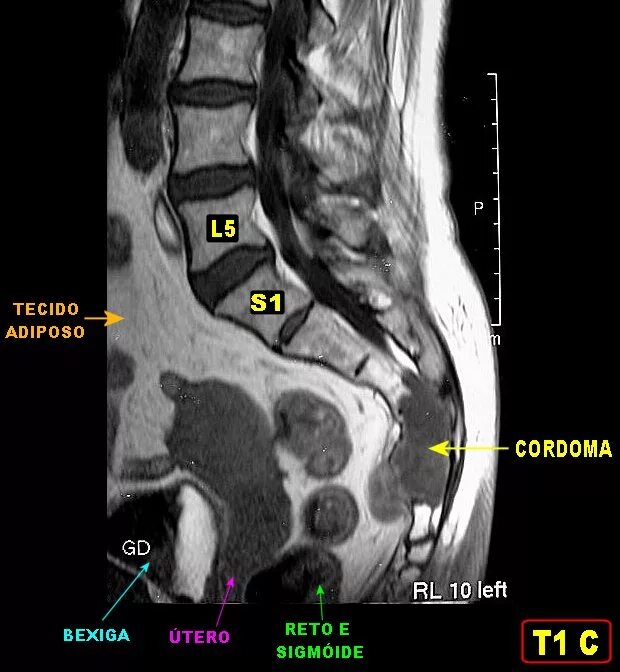

Метастазы в крестце